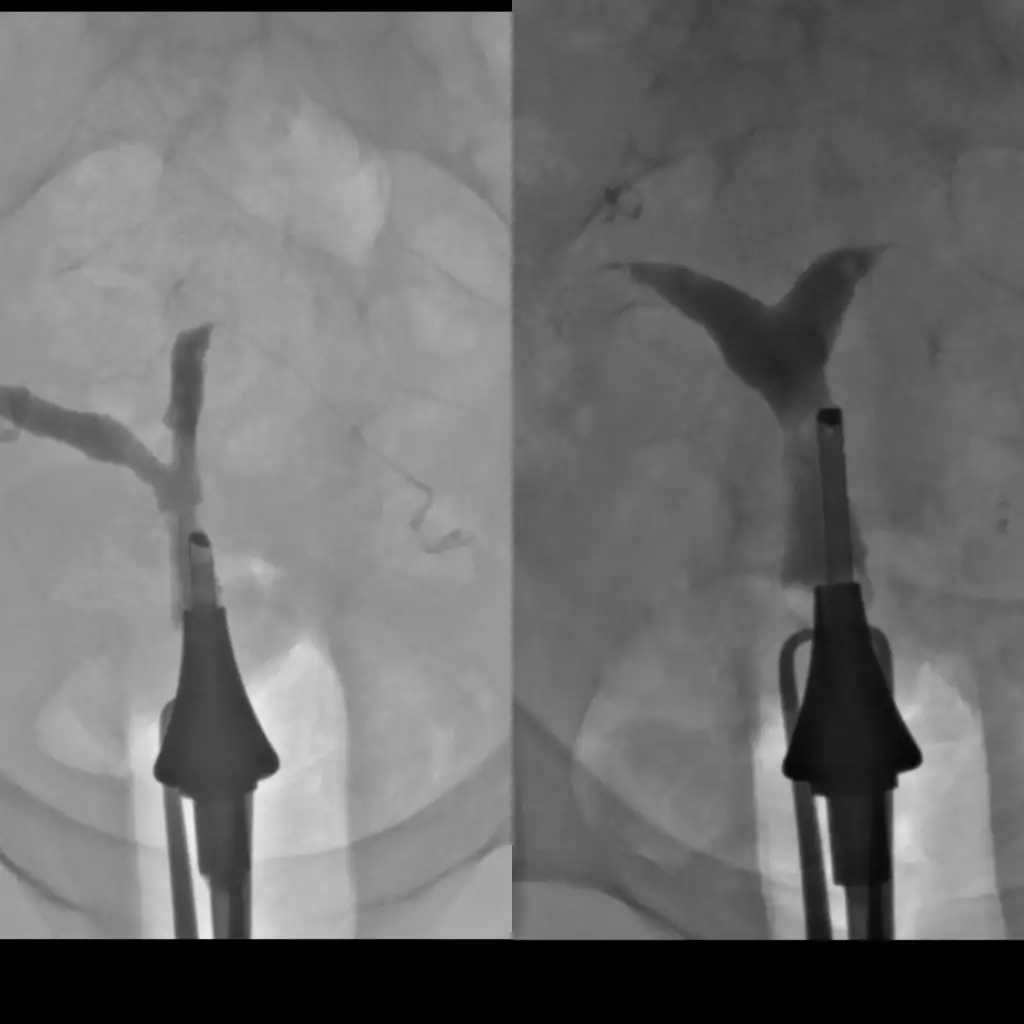

Bence ultrasondan anlaşılacak bir şey değil ben 3 ke çektirdim bu filmi. Ameliyat öncesi ve sonrası çektirdim. Sonrasında gördük ki doktor iyice perdeyi alamamış. Ve bu yüzden ikinci ameliyati oldum. Sonrasında yine bu filmden çektirdim ve malesef yine tam alnamadı perde.. en son dokuz Eylül üniversitesi hastanesinde prof tarafından yapıldı. Ve normale dondu rahim.

• CollageMaker_20200315_203515582.webp

CollageMaker_20200315_203515582.webp

12,5 KB · Görüntüleme: 150